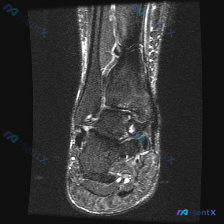

踝关节MRI被怀疑软骨异常?看看这份影像分析怎么说

拿到这份踝关节冠状位T2序列MRI,一开始问题问的是有没有软骨异常,我整理了完整读片和分析思路,大家一起看看。 一、先看影像基本信息 这是踝关节冠状位T2加权MRI,我们逐层梳理所有结构的表现: 1. 骨性结构:胫骨、腓骨远端和距骨形态完整,没有明显骨折线,骨髓信号整体尚可,但距骨内部和踝关节周围部...